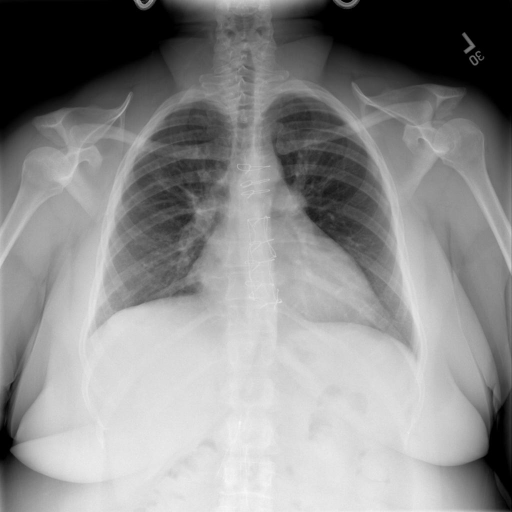

## 本文贡献  - 借助ChatGPT以及公开的数据集,我们构造了一个`X光影像-诊断报告`对的医学多模态数据集; - 我们将构建的中文胸部X光片诊断数据集在[VisualGLM-6B](https://github.com/THUDM/VisualGLM-6B)进行微调训练,并开放了部分训练权重用于学术研究; ## 数据集 - [MIMIC-CXR](https://physionet.org/content/mimic-cxr-jpg/2.0.0/)是一个公开可用的胸部X光片数据集,包括377,110张图像和227,827个相关报告。 - [OpenI](https://openi.nlm.nih.gov/faq#collection)是一个来自印第安纳大学医院的胸部X光片数据集,包括6,459张图像和3,955个报告。 在上述工作中,报告信息都为非结构化的,不利于科学研究。为了生成合理的医学报告,我们对两个数据集进行了预处理,并最终得到了可以用于训练的**英文报告**。除此之外,为了更好的支持中文社区发展,借助ChatGPT的能力,我们将英文报告进行了中文翻译,并最终形成了可用于训练的数据集。 |数据集|数量|下载链接| |:-|:-|:-| |MIMIC-CXR-zh|-|-| |OpenI-zh|6,423|[诊疗报告(英文)](./data/openi-en.json)、[诊疗报告(中文)](./data/Xray/openi-zh.json) 、[X光影像](https://pan.baidu.com/s/13GBsDMKf6xBZBSHpoWH_EA?pwd=k9sh)| ## 快速上手 1. 安装环境 ```bash # 安装依赖 pip install -r requirements.txt # 国内换源安装依赖 pip install -i https://mirrors.aliyun.com/pypi/simple/ -r requirements.txt ``` 此时默认会安装`deepspeed`库(支持`sat`库训练),此库对于模型推理并非必要,同时部分`Windows`环境安装此库时会遇到问题。 如果想绕过`deepspeed`安装,我们可以将命令改为: ```bash # 安装依赖 pip install -i https://mirrors.aliyun.com/pypi/simple/ -r requirements_wo_ds.txt # 安装SwissArmyTransformer pip install -i https://mirrors.aliyun.com/pypi/simple/ --no-deps "SwissArmyTransformer>=0.3.6" ``` 2. 模型推理 |模型权重|下载链接| |:-|:-| |checkpoints-XrayGLM-300|-| |checkpoints-XrayGLM-3000|-| CLI推理: ```python python cli_demo.py --from_pretrained checkpoints/checkpoints-XrayGLM-3000 --prompt_zh '详细描述这张胸部X光片的诊断结果' ``` 更多[参数](https://github.com/WangRongsheng/XrayGLM/blob/main/cli_demo.py#L16) ## 效果展示 影像诊断: |X光影像|诊疗报告(医生)|XrayGLM| |:-|:-|:-| ||根据X射线图像,心脏大小正常,肺部看起来很清晰。已经排除了肺炎、积液、水肿、气胸、腺病、结节或肿块的存在。该发现表明一切正常。换句话说,总体印象是胸部正常。|X光片显示,心脏大小正常。肺部没有气胸或胸腔积液的证据。骨骼结构看起来没有任何异常。总的来说,X光片表明没有发现急性心肺疾病的迹象。| ||X光图片显示没有扭曲的区域、可疑的骨质不透明度或胸腺积液。心脏大小轻微增大,但非常稳定。此外,没有气胸的证据,肺野也正常。总体来说,X光片显示没有急性心脏异常,但要注意轻微的心脏扩大。|X光片显示,心脏大小正常。肺部和纵隔轮廓清晰,没有气胸或胸腔积液的证据。骨骼结构完整,没有任何急性异常。| ||心影形态在正常范围内。没有急性骨质异常。有可能出现没有明显的吸水或肺实质状况的线索。没有大面积积液或气胸。有可能怀疑其有误吸或肺实质问题。为了确诊和治疗,可能需要进行适当的影像学随访。|心脏大小正常,肺部和纵隔轮廓清晰。没有急性异常或活动受限的证据。没有任何明显的气胸、胸腔积液或肺不张的迹象。此外,也没有发现任何局灶性骨质异常或其他急性疾病。| 多轮对话: |X光影像|诊疗报告(医生)| |:-|:-| ||右侧主动脉突出观察到。心脏大小正常。胸部未发现明显的肺气肿、胸膜积液或可疑的肺部病变。报告指出已知右侧主动脉情况正常。| ```bash >> X光影像路径:./data/Xray/861_1.png >> 用户:这是一张什么图? >> XrayGLM:这张图片显示的是一张肺部检查的X光片。 >> 用户:请描述这张胸部X光片的诊断结果 >> XrayGLM:心脏大小正常,肺部清晰。没有急性心肺疾病的证据。 >> 用户:是否存在肺气肿? >> XrayGLM:没有肺气肿。心脏大小正常,肺部清晰。没有发现急性心肺疾病的证据。 >> 用户:平时饮食该注意什么? >> XrayGLM:饮食应该健康,均衡。建议增加蛋白质的摄入量,因为蛋白质有助于维持肌肉和骨骼的健康。多食用蔬菜、水果、全谷物以及健康的脂肪来源如橄榄油、鱼类等可以帮助获得足够的维生素和矿物质。此外,避免过度饮酒或吸烟,这些习惯可能会对心脏健康产生负面影响。 ``` ## 未来展望 1. 模型的能力更多来源于数据的支持,`OpenI-zh`作为微调数据集,其数据量足以支持研究,在更广泛的任务和性能表现上,我们认为**在大规模数据集上预训练并在高质量少量数据集上微调是一种可行的方案**; 2. 普遍意义的理解上,视觉多模态模型=视觉模型+语言模型。除了需要关注视觉模型信息与语言模型输出的搭配外,还需要**额外关注到语言模型的加强,在人机的对话中,尤其是医疗语言模型的问答上,除了专业的医疗问题回答,带有人文情怀的有温度的回答更应该是我们追寻的目标**。 ## 项目致谢 1. [VisualGLM-6B](https://github.com/THUDM/VisualGLM-6B)为我们提供了基础的代码参考和实现; 2. [MiniGPT-4](https://github.com/Vision-CAIR/MiniGPT-4)为我们这个项目提供了研发思路; 3. ChatGPT生成了高质量的中文版X光检查报告以支持XrayGLM训练; 4. [gpt_academic](https://github.com/binary-husky/gpt_academic)为文档翻译提供了多线程加速; 5. [MedCLIP](https://github.com/RyanWangZf/MedCLIP) 、[BLIP2](https://huggingface.co/docs/transformers/main/model_doc/blip-2) 、[XrayGPT](https://github.com/mbzuai-oryx/XrayGPT) 等工作也有重大的参考意义;  这项工作由[澳门理工大学应用科学学院](https://www.mpu.edu.mo/esca/zh/index.php)硕士生[王荣胜](https://github.com/WangRongsheng) 、[段耀菲](https://github.com/IsBaSO4) 、[李俊蓉](https://github.com/lijunrong0815)完成,指导老师为檀韬副教授、[彭祥佑](http://www.patrickpang.net/)老师。 *特别鸣谢:[USTC-PhD Yongle Luo](https://github.com/kaixindelele) 提供了有3000美金的OpenAI账号,帮助我们完成大量的X光报告翻译工作 ## 免责声明 本项目相关资源仅供学术研究之用,严禁用于商业用途。使用涉及第三方代码的部分时,请严格遵循相应的开源协议。模型生成的内容受模型计算、随机性和量化精度损失等因素影响,本项目无法对其准确性作出保证。即使本项目模型输出符合医学事实,也不能被用作实际医学诊断的依据。对于模型输出的任何内容,本项目不承担任何法律责任,亦不对因使用相关资源和输出结果而可能产生的任何损失承担责任。 ## 项目引用 如果你使用了本项目的模型,数据或者代码,请声明引用: ```bash @misc{wang2023XrayGLM, title={XrayGLM: The first Chinese Medical Multimodal Model that Chest Radiographs Summarization}, author={Rongsheng Wang, Yaofei Duan, Junrong Li, Patrick Pang and Tao Tan}, year={2023}, publisher = {GitHub}, journal = {GitHub repository}, howpublished = {\url{https://github.com/WangRongsheng/XrayGLM}}, } ``` ## 使用许可 此存储库遵循[CC BY-NC-SA](https://creativecommons.org/licenses/by-nc-sa/4.0/) ,请参阅许可条款。